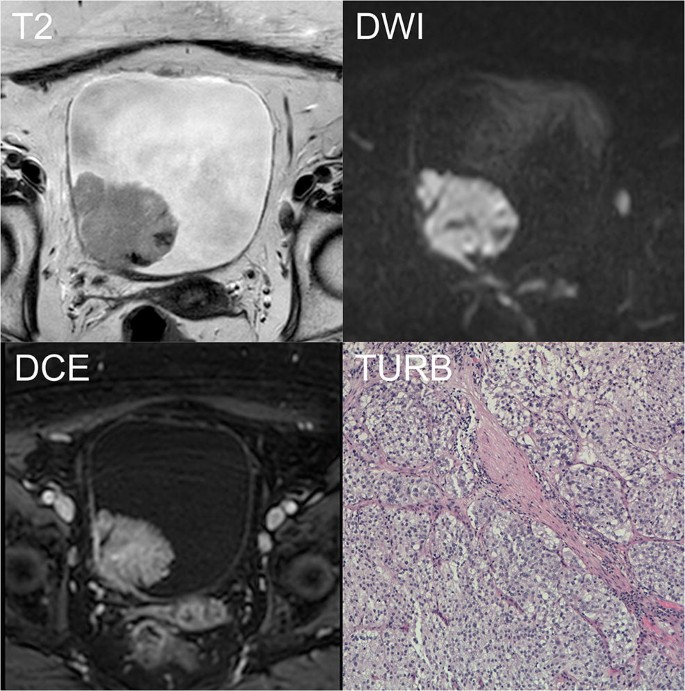

Magnetic resonance imaging (mri) provides a useful alternative to ct scanning in individuals at risk for encoded search term (kidneys%2c ureters%2c and bladder (kub) imaging) and kidneys. 13 evaluating the ability of mri in staging bladder tumors without dwi, but with enhanced and unenhanced sequences, the agreement among reviewers was good (kappa = 0.80) and accuracy in. Magn reson imaging clin n am.

The study allows to detect the tumor and to determine its location with millimeter. Bladder cancer is any of several types of cancer arising from the tissues of the urinary bladder. Indications for mri urinary bladder. Learn about other bladder cancer signs and symptoms and explore treatment options.